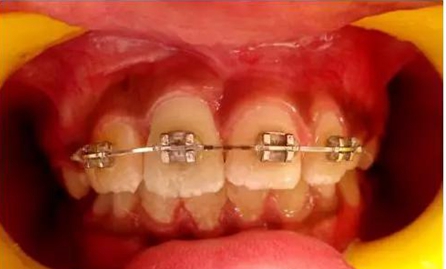

正畸牽引5周后,牙齒復位到其原始位置,與其他切牙完全對齊(圖3)。開始嘗試血運重建。重新打開根管,使用次氯酸鈉和生理鹽水沖洗。然后插入無菌根管銼,并將其推到根尖處,以使血流進入根管。一旦血液到達釉牙骨質界,放置一個濕潤的無菌棉球靜置15分鐘,直到血凝塊形成,再放置約2-3mm的MAT在血凝塊上。在MAT上覆蓋一個濕棉球,隨后進行臨時修復。以后再替換為玻璃離子水門汀墊底和復合樹脂修復。復診時間為1、3、6、9和12月。正畸復位保留12周。然而,在這么長的保留期內還是復發(fā)了錯位,這也強調了在嚴重侵入的情況下長期復位的重要性,因為累及的牙齒周圍出現(xiàn)大量的牙槽骨喪失(圖 4)。

牙齦: 即使病人保持良好的口腔衛(wèi)生,在正畸治療完成后,在受累的牙齒上能觀察到明顯的牙齦萎縮。系帶附著位置可能是原因之一。修整系帶可能可以解決這個問題(圖4)。在軟組織愈合后,復發(fā)的牙齒復位至正常位置(圖 5)。經過6周病人細致的口腔衛(wèi)生維護,牙齦狀況和美觀得到改善(圖6和7)。